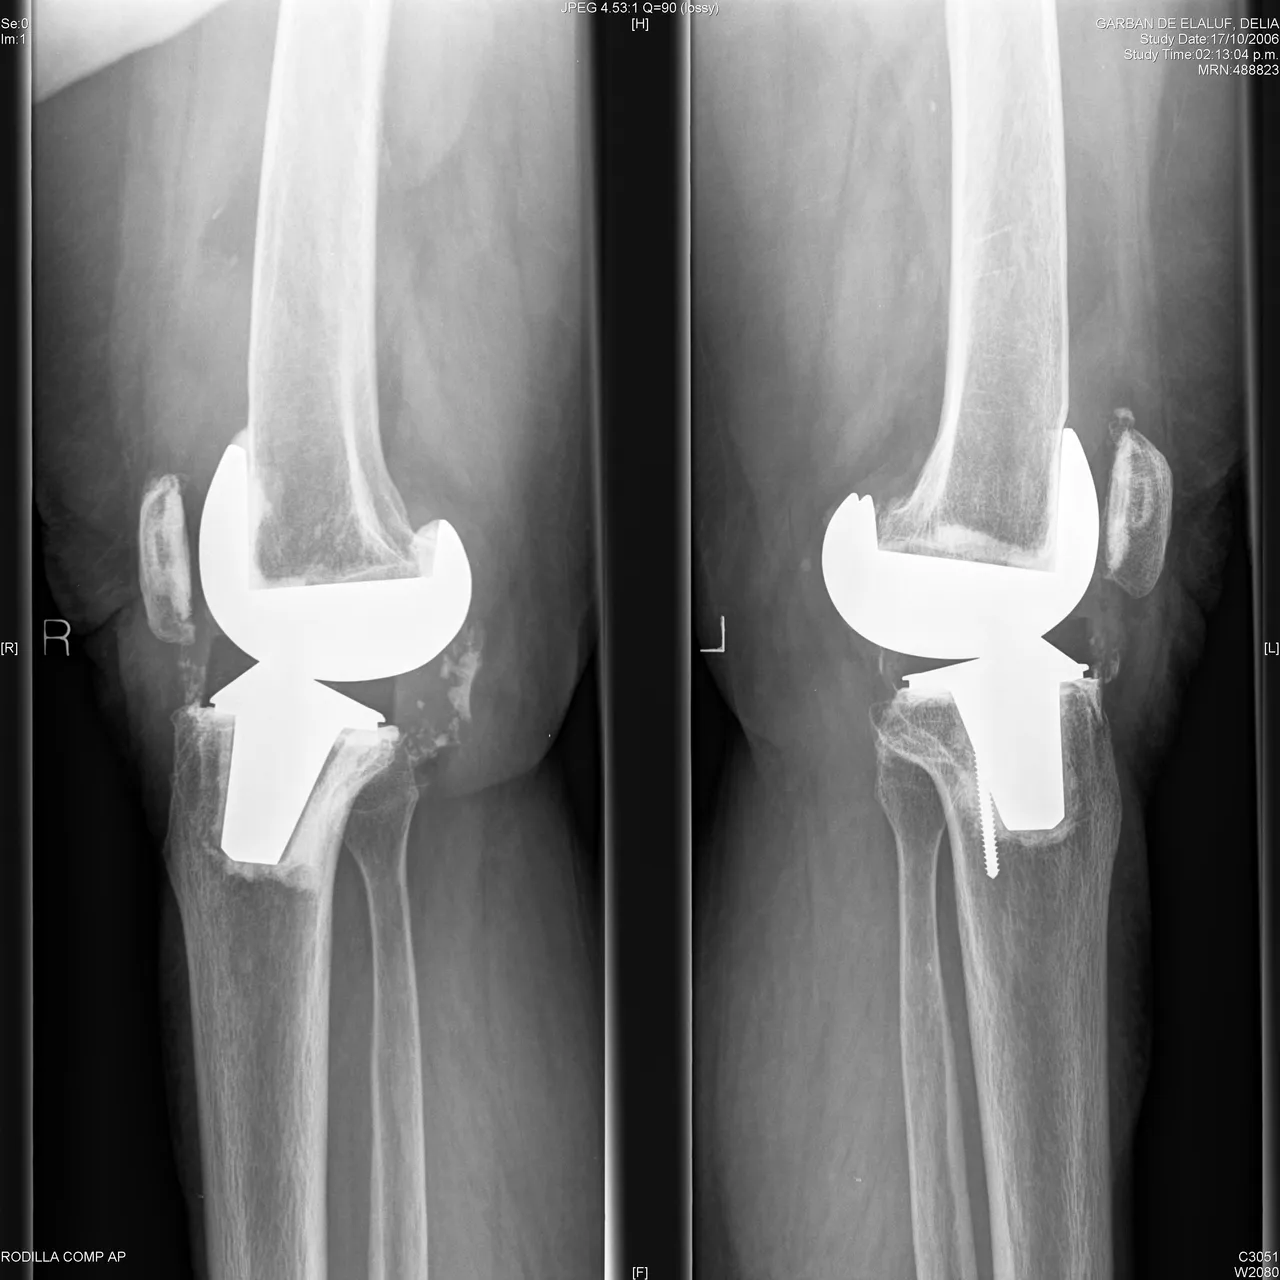

Recent studies mention that practicing bilateral arthroplasty consecutively increases satisfaction and good functional status in patients over 75 years of age. When performing comparative studies between bilateral and unilateral prostheses, the results in both were good, although the cardiovascular risk increased in bilateral prostheses during the postoperative period. In a report from China, bilateral arthroplasty in people with rheumatoid arthritis improved pain and function in all patients, wounds healed without problems, few cases of thrombophlebitis were found and a low infection rate in 45 post-operative patients, which showed that using the consecutive technique has the following advantages: low cost, savings in blood loss, reduced risk of anesthesia, the effect of the drugs administered and hospitalization time, which facilitates early rehabilitation.

There are studies that compare the placement or not of patellar component in bilateral arthroplasties, with similar results, only that when no patellar component was placed, they presented pain when standing or going up and down stairs; our patients did not receive the patellar component. The type of system to be used was compared in Switzerland, analyzing the advantages of each one; no long-term differences were found; yes with asymmetries in the movement of the patient in the mentioned systems. We consider that the system used is the one the surgeon handles best; the advantages provided by new systems on the market are recognized beforehand, purifying the surgical time for their placement.

Other studies show us their experience when comparing unilateral and bilateral treatments; again, they find more benefits when performed consecutively: lower cost, excellent functional results, short rehabilitation period and bilateral benefit, in addition the risks are minimal compared worldwide and the greater benefits compared with a unilateral form; the best, the patient's satisfaction and his integral benefit.